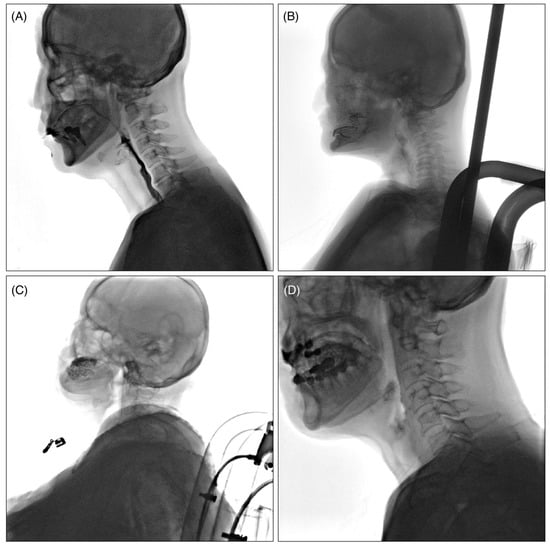

The collected VFSS videos were classified into four levels, Q1 to Q4, according to the quality of the images, with the criteria as follows (Figure 1): Q1: videos in which the airway and epiglottis are clearly visible without artifacts; Q2: videos in which the epiglottis is clearly visible but the airway is partially obscured due to the shoulders; Q3: videos with severe bolus transit issues during the oral phase, making it difficult to adequately assess the pharyngeal phase; and Q4: videos with multiple artifacts caused by buttons, previous surgeries, thyroid calcification, etc.

Figure 1. Example of classification according to VFSS video quality. (A): Q1; videos in which the airway and epiglottis are clearly visible without artifacts, (B): Q2; videos in which the epiglottis is clearly visible but the airway is partially obscured due to the shoulders, (C): Q3; videos with severe bolus transit issues during the oral phase, making it difficult to adequately assess the pharyngeal phase, (D): Q4; videos with multiple artifacts caused by buttons, previous surgeries, thyroid calcification, constant moving of the patients’ head, etc.